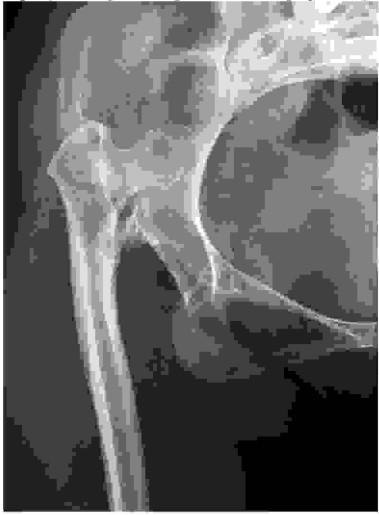

Poniższy radiogram stawu biodrowego przedstawia koksartrozę dysplastyczną: Wskaż jej stopień wg klasyfikacji Crowe'a: